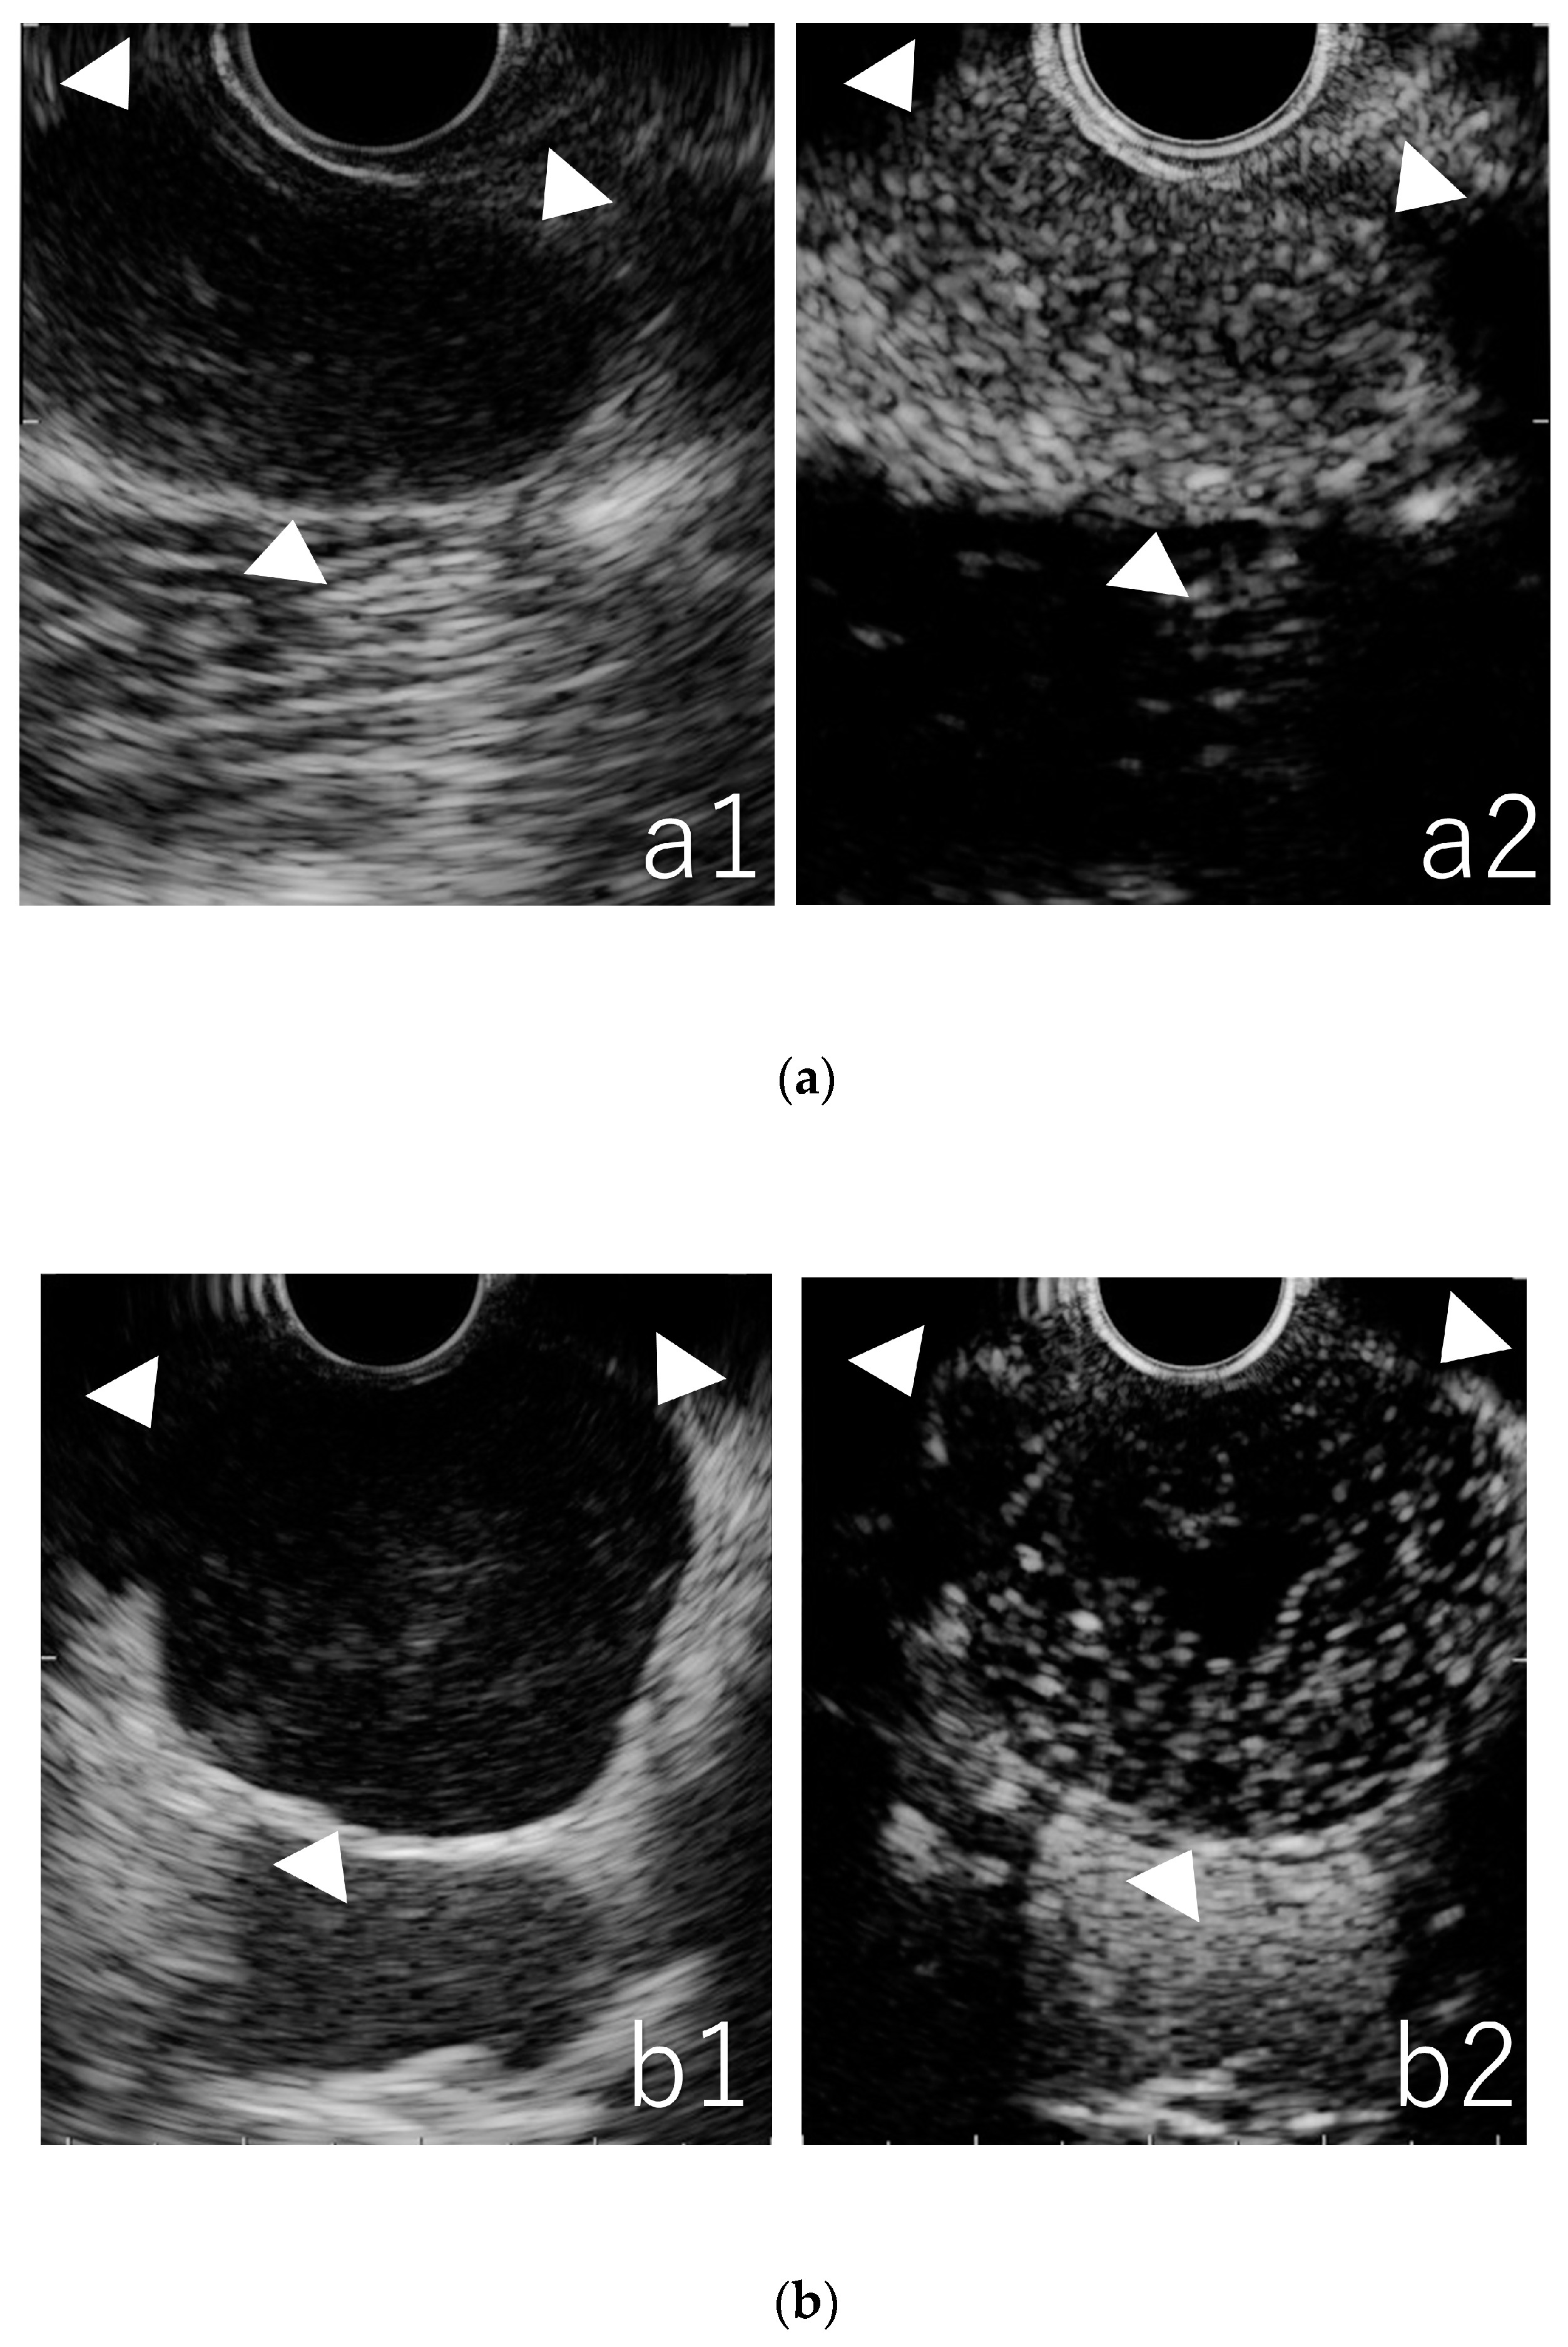

3.3. Qualitative Evaluation in CE-EUS

3.4. Quantitative Evaluation in TIC